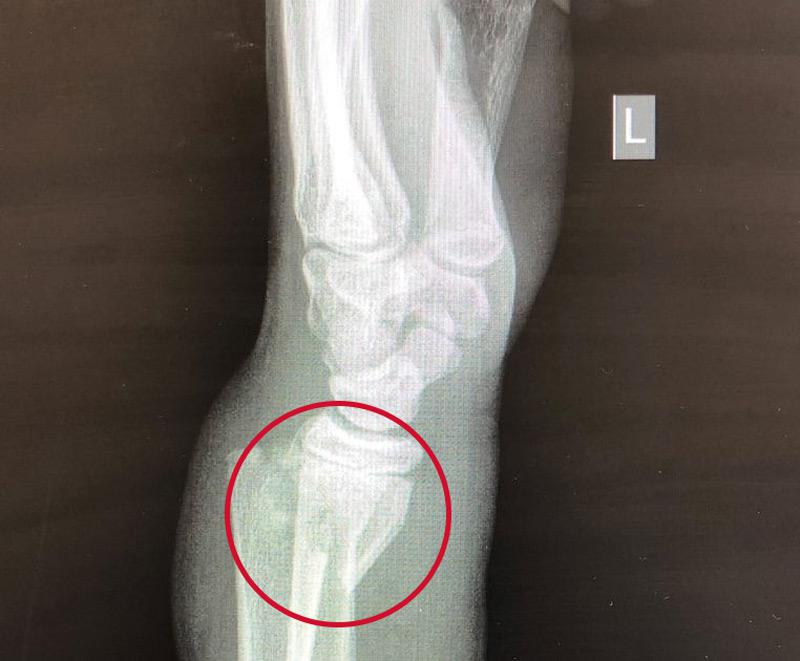

A Smith fracture is diagnosed with an X-ray. This tells your healthcare provider which of your bones are broken and which type of fracture you have. All broken wrists require an X-ray.

In addition to confirming your broken wrist, the X-ray will give your healthcare provider important information such as how clean the break is or how many pieces there are, how much space there is between your bones and whether other bones are damaged, too.